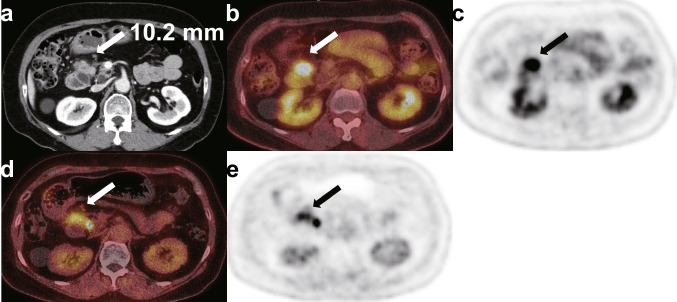

Results: [18F]AIF-FAPI-74 PET/CT showed a significantly higher maximum standardized uptake value than [18F]FDG PET/CT did in evaluating primary pancreatic lesions (median [interquartile range]; 12.6 [10.7-13.7] vs. 6.3 [4.8-9.2]; P < 0.001). In contrast, [18F]AIF-FAPI-74 PET/CT showed a significantly lower mean standardized uptake value than [18F]FDG PET/CT did in evaluating background organ (median [interquartile range]) 0.8 [0.7-0.9] vs. 2.6 [2.3-2.7]; P < 0.001). In addition, the sensitivity of [18F]AIF-FAPI-74 PET/CT in detecting metastatic lymph nodes was higher than that of [18F]FDG PET/CT (50.0% vs. 0.0%; P = 0.026).